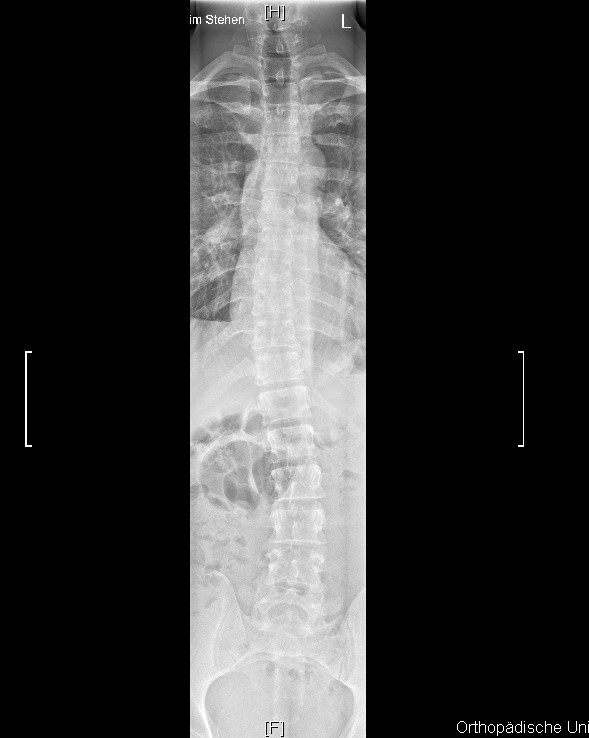

Das bringt mich zu meinem eigentlichen Punkt: Ich habe aktuelle Röntgenaufnahmen anfertigen lassen. Der zuständige Orthopäde meinte, mein Krümmungswinkel LWS läge bei 22 Grad. Vor knapp zehn Jahren hieß es, es seien 12 Grad LWS. Etwas mehr als 1 Grad Verschlechterung pro Jahr bei diesem für Skoliose-Verhältnisse geringen Krümmungswinkel - das macht mich hellhörig.

Die Röntgenbilder habe ich angehängt. Habt ihr Erfahrungen mit Messfehlern und -ungenauigkeiten? Sind diese zehn Grad Verschlechterung auch anhand der Bilder realistisch? Vielen Dank für euere Meinungen.

10 ist die alte Aufnahme, 20 die aktuelle. Das CT stammt von 2019 und wurde im Liegen angefertigt. Die RB im Stehen.

- rb_lende_20.jpg (58.24 KiB) 9050 mal betrachtet

- roentgen_20_neu.jpg (44.85 KiB) 9050 mal betrachtet

Ja da sieht man es, eindeutig

Die Diagnose des Orthopäden sind die angesprochenen 22 Grad und eine Verschlechterung um 10 Grad im Vergleich zum alten Bild.

Meine WS hat unten 18 Grad und sieht ähnlich aus wie Deine mit 22 Grad. Das mit den 22 Grad könnte also leider hinkommen. Ca. 1 Grad Verschlechterung pro Jahr sind bei Erwachsenen "normal", da bist Du voll im Rahmen. Ich habe auch vor allem im LWS-Bereich Verspannungen. Dehnungen für den Psoas- bzw. Illiopsoas-Muskel helfen mir zumindestens stundenweise. Manchmal schaffe ich es damit, sogar stundenweise fast schmerzfrei zu werden, das ist dann ein sehr schönes Gefühl. Mit einem Osteopath, der >100 € pro Stunde kostet, habe ich gute Erfahrungen gemacht. Er hat endlich herausgefunden, welche Muskeln mit hauptsächlich die Schmerzen verursachen. Vor allem die Übung, die meine Gesäßmuskulatur dehnt, hilft sehr aber leider vor allem temporär. So nach 2-3 Stunden habe ich das Gefühl, dass wieder alles beim alten ist. Vielleicht tut sich langfrist auch so langsam was, kann ich aber noch nicht mit Sicherheit sagen, da ich die Übungen erst seit ca. 1 Woche mache.

Keine Ahnung, ob das aussagekräftig ist, aber ... ich habe die beiden Röbis in der LWS mal auf die gleiche Größe gezogen anhand des untersten Wirbels und in Photoshop übereinandergelegt und dann jeweils die Transparenz verschoben. Bei diesem Vergleich habe ich zumindest visuell keine große Abweichung der Verbiegung gesehen. Der Doktor sprach von einer Messungenauigkeit von drei Prozent. Wenn er drei Prozent zu viel gemessen hat und der Doktor damals drei Prozent zu wenig ...